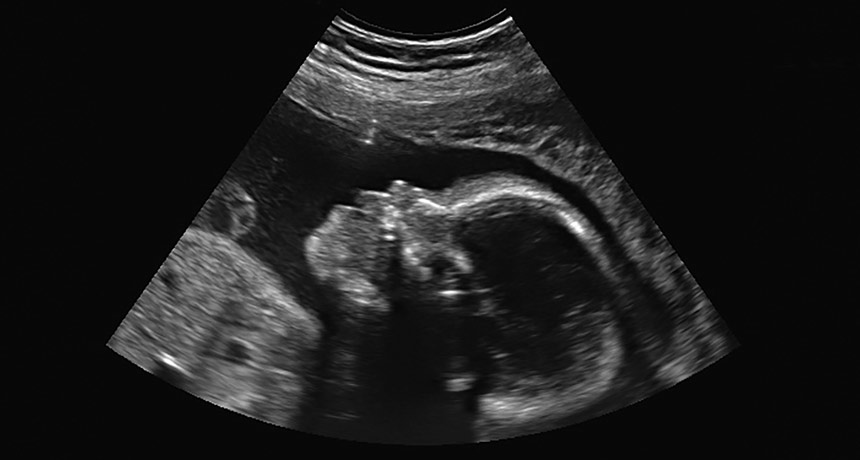

PEEK INTO THE WOMB While still growing in the womb, a fetus’s full genome can be tested, but the approach should be limited to special cases, three medical groups say.

Decades ago, pregnant women had to wait about 40 weeks before knowing much about their baby. But swiftly moving technology offers increasingly detailed peeks into the womb.

Beyond generating adorable 3-D ultrasounds of scrunched-up faces, researchers can now analyze a fetus’s full genome from a simple blood draw from mom. But these genome-wide prenatal tests are not ready for prime time, three medical organizations argued in a position paper in the January Prenatal Diagnosis.